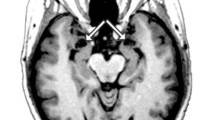

An undated image of a brain scan provided by the University of Iowa Department of Neurology, shows an MRI scan of patient SM’s brain. The arrows point to the amygdala, the region of the brain which SM is missing, as shown by the vacant black holes underneath the arrows. (AP Photo/University of Iowa Department of Neurology)